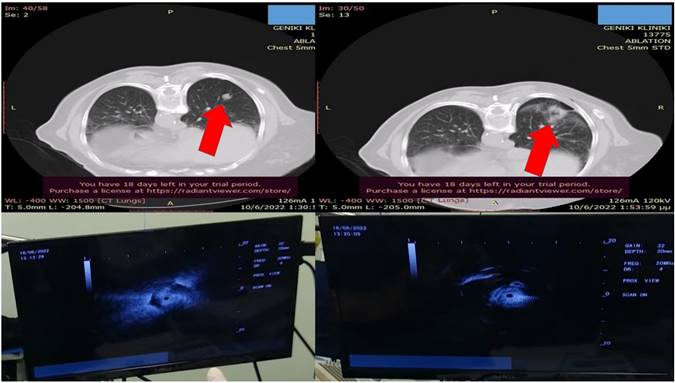

Figure 1

Demonstrates the positron emission tomography findings upon diagnosis red arrow indicates the pulmonary nodule.

Figure 2

Left upper row red arrow indicates the lesion before ablation, left lower row demonstrates the lesion sign with radial ebus, right upper row red arrow indicates the area after 2 sessions of thermal effect with radiofrequency ablation, right lower row demonstrates the lesion sign after the ablation.